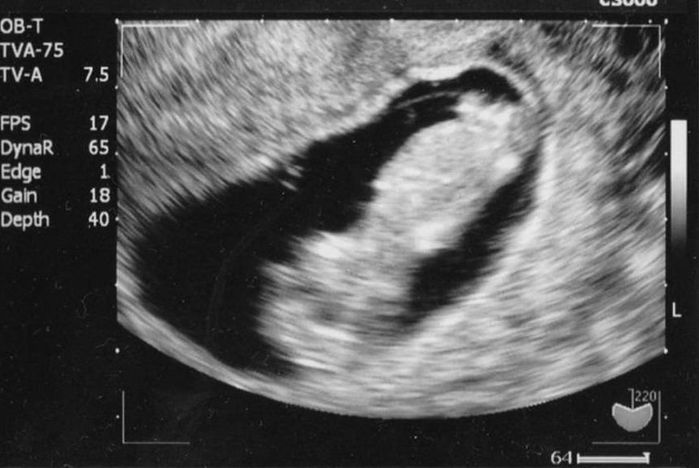

妊娠4週目のエコー写真

妊娠が確定した日、かねてからの憧れだった雑誌「たまごクラブ」を買いに行きました。妊娠経験や出産体験を見るため口コミサイト「ウィメンズパーク」に早速登録し、同じ月齢の妊婦さんのページから情報を集めました。初めて知る内容は興味深く、夜遅くまで読みふける毎日。